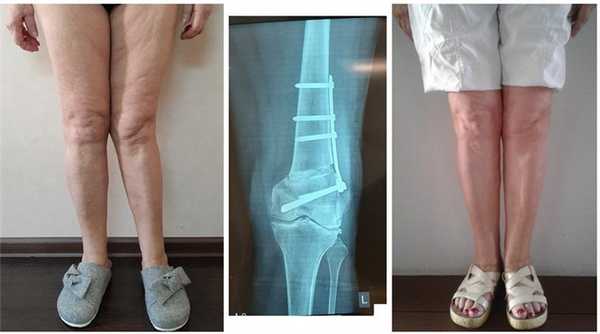

Часто встречающаяся ситуация - вальгусная деформация ног + наружная ротация + укорочение левого бедра 2 см. Слева деформация более выражена, поскольку деформированы были и бедро, и голень. Провели двухэтапную коррекцию. 1 этап - левое бедро, 2 этап - обе голени. Genu valgum (в отличие от genu varum) часто обусловлена деформацией бедренных костей. Поэтому для определения объема операции обязательно нужен рентген ног по всей длине.

При такой значительной деформации уже к 50 годам развивается деформирующий артроз коленных суставов преимущественно с вовлечением наружных отделов. Когда деформация прогрессирует, операция по исправлению оси становится уже не настолько эффективна. Кроме того, вальгусное колено намного сложнее в плане эндопротезирования.

Достаточно грубая варусная деформация у девушки 25 лет исправленная при помощи метода Илизарова. У аппаратной методики есть важное преимущество, она позволяет производить коррекцию в любых плоскостях, одновременное увеличение длины, и одновременно проводить вмешательство на обеих нижних конечностях. Аппарат Илизарова можно спрятать под свободными брюками, и ходить без трости или костылей. Подобная операция не только является профилактикой развития в последующем гонартроза с поражением внутренних отделов коленных суставов, но так же значительно влияет на эстетику нижних конечностей, что крайне важно, когда мы говорим о девушках.